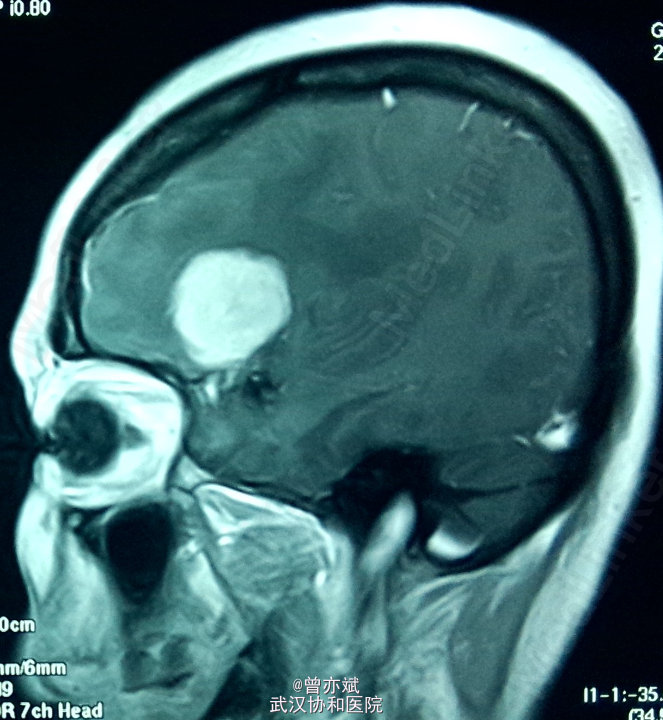

蝶骨嵴 or 大脑凸面脑膜瘤?

患者女,48岁,因“头晕1年”入院。近来出现左侧肢体肌力下降。

查体除左侧肢体肌力稍差4+,余无阳性体征。MRI如下